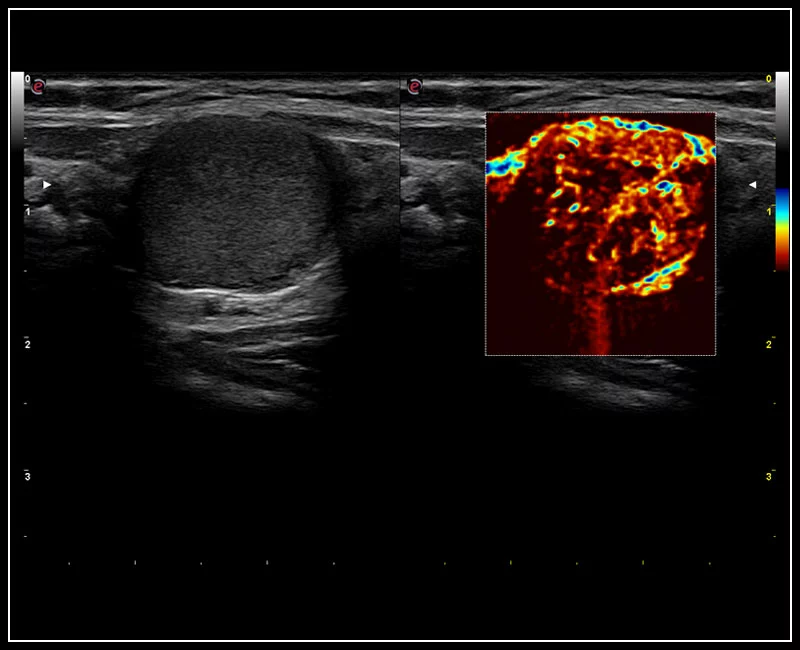

MyLab™9 Platform - High resolution imaging in testis

MyLab™9 Platform - High resolution imaging in testis